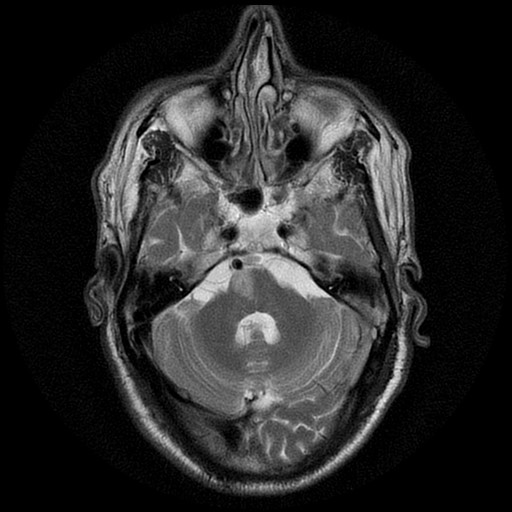

- ↑ Image courtesy of Dr Mohammad A. ElBeialy, Radiopaedia.org, rID: 29951. Used under CC BY-NC-SA 3.0 (https://creativecommons.org/licenses/by-nc-sa/3.0/)